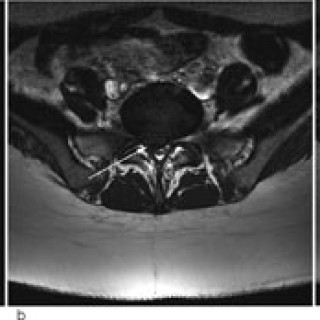

En 40 år gammel kvinne ble innlagt i medisinsk avdeling til utredning for anemi (1). Hun hadde tidligere vært frisk, men hadde de siste månedene før innleggelsen følt seg tiltakende slapp og tungpustet. I en periode hadde hun hatt rikelige og langvarige menstruasjoner. Av egen lege hadde hun fått jerntabletter, men hadde likevel Hb 6,8 g/100 ml. Ved innleggelsen var pasienten i noe redusert allmenntilstand, blek, men med uanstrengt respirasjon. Organstatus var normal, bortsett fra at man mente å kunne palpere uterus. Blodprøvene viste følgende verdier: Hb 6,5 g/100 ml, leukocytter 6,0 · 10⁹/l...